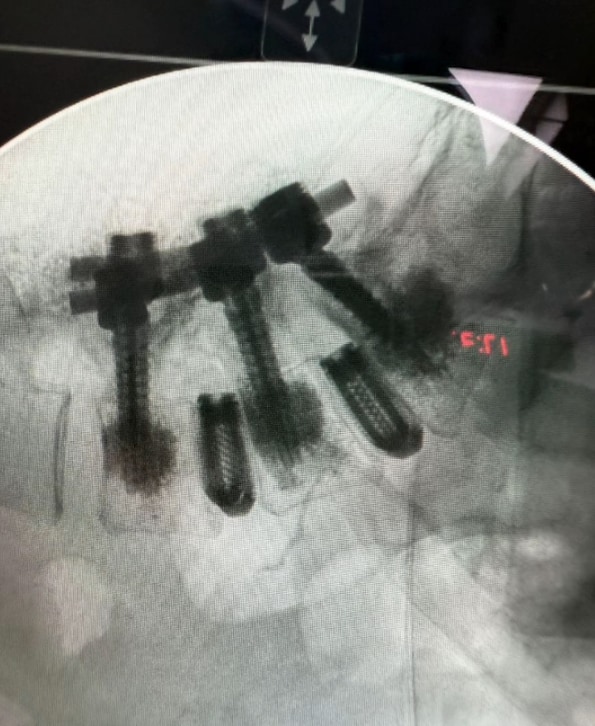

Alejandra también aprovechó la oportunidad para mostrar una radiografía en la que evidencia el proceso y los resultados de su cirugía. Aunque no dio detalles puntuales de lo que implicó la operación, en una entrevista pasada habló de su problema con las cervicales, por lo que todo indica que ahora ha puesto todo de su lado para atender ese padecimiento. “Es increíble cómo me siento, cómo estoy de bien operada. Hay mucho más, vamos a seguir adelante, vamos a seguir brillando y vamos a seguir siendo felices, los amo”, reiteró la cantante en su mensaje, el cual causó gran sorpresa entre sus fieles seguidores.

Meses atrás, Alejandra dio a conocer que había sido intervenida de las cervicales, lo que implicó que le colocaran piezas de titanio como parte de su tratamiento. Mientras tanto, la cantante se ha tomado el tiempo para recuperarse de manera favorable, por lo que ha pospuesto sus presentaciones del 2025 hasta el año 2026, según dio a conocer semanas atrás en un comunicado.